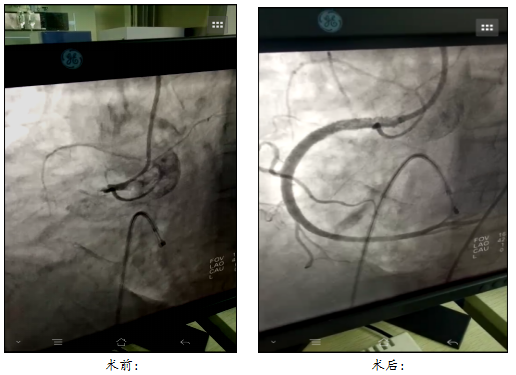

假期第二天,一位77岁女性患者因“精神差、上腹部不适2天”入院,糖尿病史多年,结合心电图诊断:急性下壁、右室心肌梗死,II度2型房室传导阻滞。当时为休克血压、心率慢,随时可能心脏停跳,生命危在旦夕,必须争分夺秒开通闭塞血管。经过与家属充分沟通,经医院胸痛中心绿色通道,行冠脉造影检查,示右冠脉闭塞、冠脉内大量血栓,在临时起搏器保驾下,反复冠脉血栓抽吸,冠脉内溶栓,多次给药,术中反复出现无复流、低血压、心律失常,手术经历了艰难的4小时,通过精心操作,准确判断,最终完成了右冠脉血运重建,再创生命奇迹。